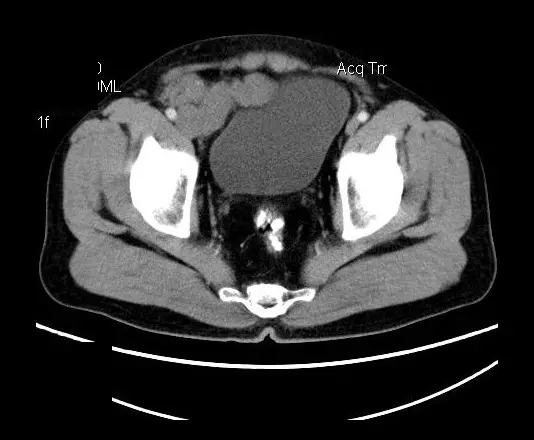

【影像表现】

盆腔右前侧及邻近腹股沟区可见多发大小不等的聚集生长的结节影,病灶呈软组织密度,边缘尚规整,分界尚清,增强扫描可见不均匀强化。膀胱局部受压,盆腔未见明显肿大淋巴结影。